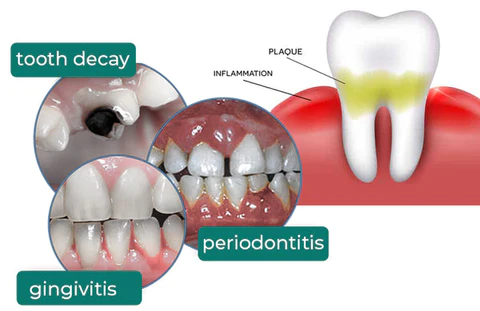

Removes tartar plaque and other oral problems. Get the confidence you deserve!

TLOPA™ Ampoule Oral Restorative Toothpaste can thoroughly whiten yellow teeth, remove tartar accumulated on teeth, solve dental plaque, and bring a comprehensive and clean oral experience. Remove bad breath, relieve tooth sensitivity, gum bleeding, etc. Solve tooth sensitivity and gum bleeding, repair gum damage and receding gums.